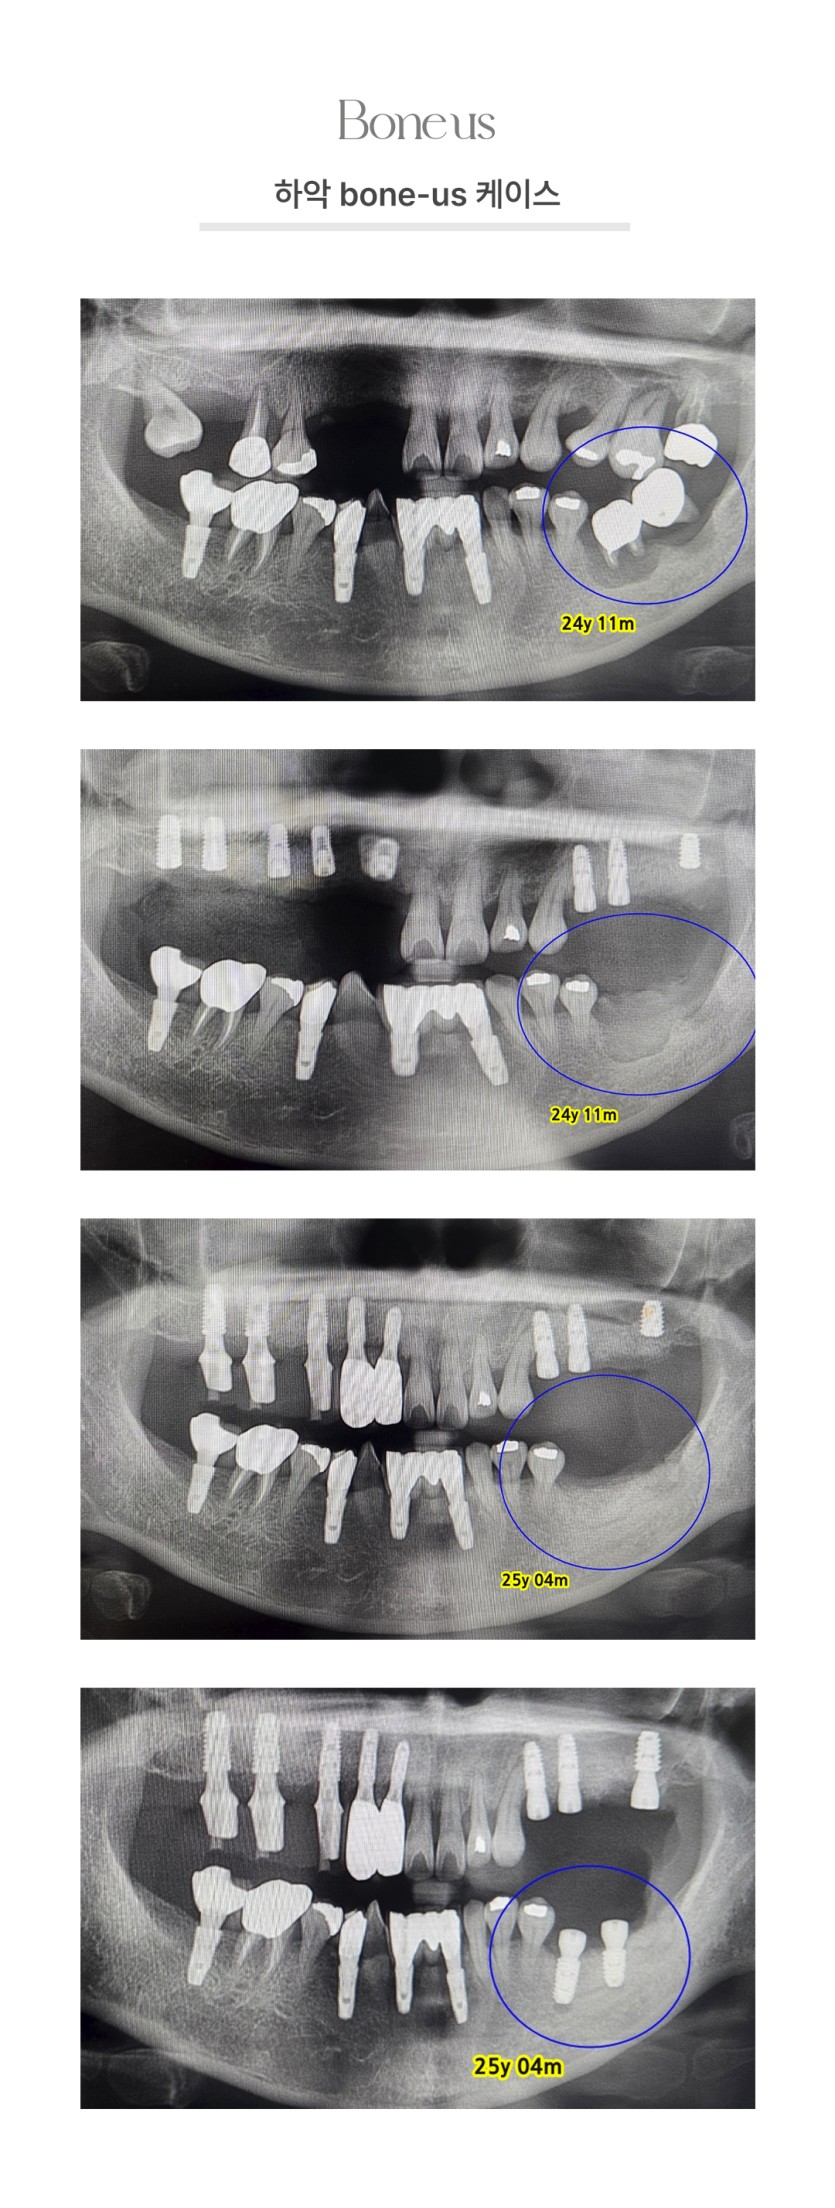

CLINICAL CASE

본어스 시술사례

하악 본어스 케이스 1

하악 본어스 케이스 2